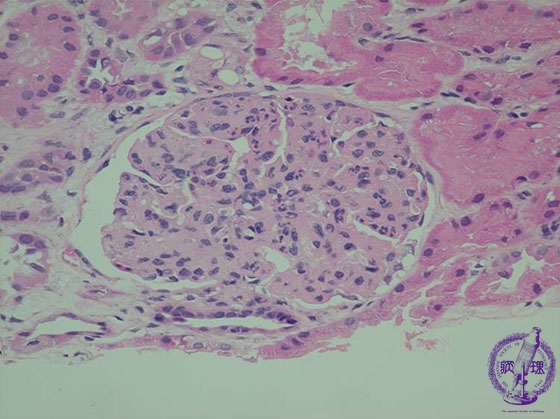

- (8)Endocapillary proliferative glomerulonephritis

Microscopic findings (HE, high power): There is an endocapillary cellular proliferation which includes neutrophils and macrophages (hypercellularity, yellow arrows).